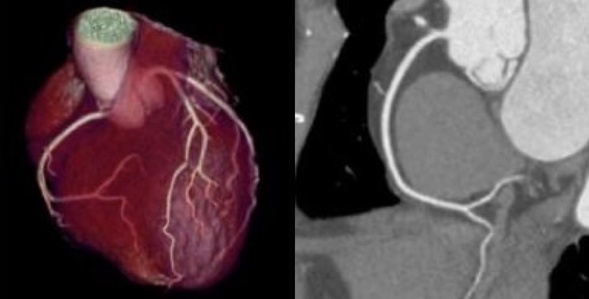

高能宽体球管可进一步提高高分辨率成像的性能,进而提升空间分辨率。对患者进行全心冠脉成像中,辐射剂量仅为0.75msv,极大降低了患者受辐射剂量;并且突破了对比剂使用禁忌,对比剂用量仅为25cc,突破了以往肾功能不全的患者无法进行增强及血管扫描的困境。

低辐射剂量低对比剂用量 1-BEAT 冠脉成像